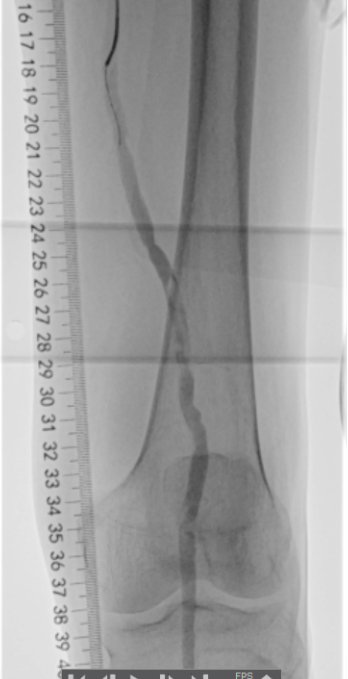

术前下肢动脉CTA提示:左下肢股、腘动脉长段闭塞,膝下动脉主干未见显影,可见少量侧支血流。

血管外科姜坤主任团队仔细分析患者病情,该患者在动脉硬化闭塞基础上继发血栓形成,且血栓负荷量大,身体状况差,行麻醉及开放手术取栓的风险大,遂制定了微创腔内的手术方案,采用动脉机械血栓清除+血管成形术。

术中选用Rotarex导管行血栓清除,对管腔内残留的血栓放置溶栓导管,最后采用球囊扩张狭窄病变,管腔获得满意。